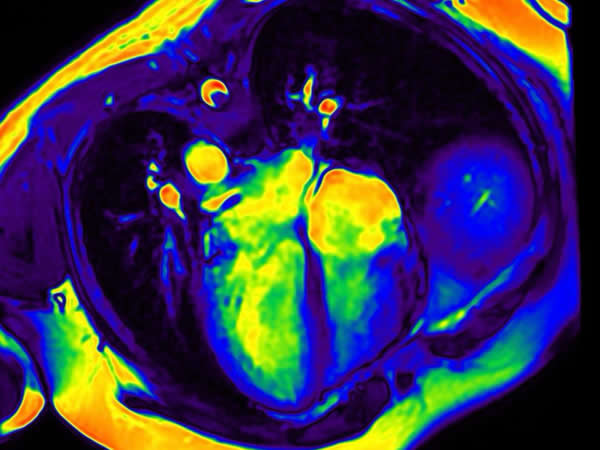

Patología aneurismática de cayado aórtico y aorta descendente torácica en paciente con dolor precordial atípico